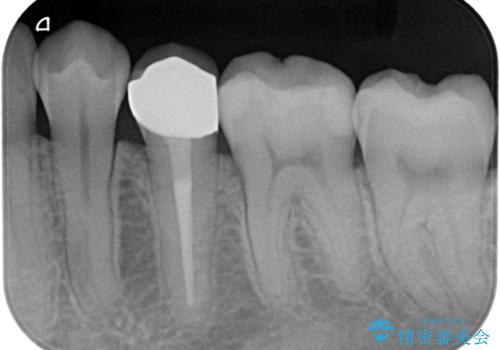

【オールセラミッククラウン】根管治療した歯の被せ物治療

- 根管治療した歯の被せ物の治療を希望され来院されました。

被せ物を行うことで、破折リスクを低下させることができます。

オールセラミッククラウン(スタンダード)で製作しています